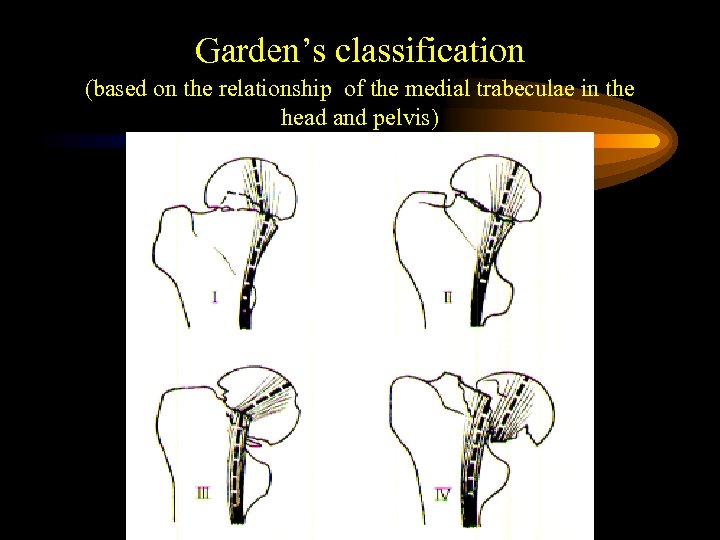

Garden’s classification (based on the relationship of the medial trabeculae in the head and pelvis)

Garden’s classification (based on the relationship of the medial trabeculae in the head and pelvis)

Fracture related pattern of femoral neck fractures representing risk for osteofixation failure, non-union and avascular necrosis • Grade of dislocation (Garden 1972, Thorngren 1991) • Size of head fragment (Benterud et al. Acta Orth Scand 1994) • Posterior comminution (Benterud et al. 1997) • Osteoporosis (Bentley 1972, Riska 1969, Anderson 1969, Thorngren 1995)

Fracture related pattern of femoral neck fractures representing risk for osteofixation failure, non-union and avascular necrosis • Grade of dislocation (Garden 1972, Thorngren 1991) • Size of head fragment (Benterud et al. Acta Orth Scand 1994) • Posterior comminution (Benterud et al. 1997) • Osteoporosis (Bentley 1972, Riska 1969, Anderson 1969, Thorngren 1995)